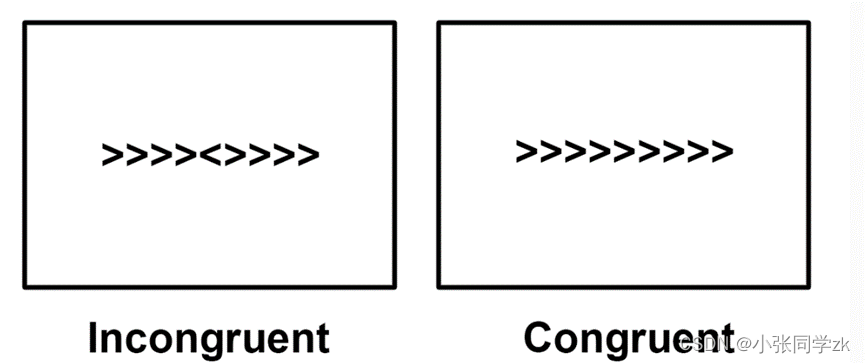

这批数据来自于spm12(https://tinyurl.com/scelanz)官网,被试需要做2个runs,如下图所示,需要对箭头的方向做出反应,箭头朝右就按右键,朝左按左键,这批数据中有被试的反应时,准确率,可以在此文件夹用txt形式打开(sub-01_task-flanker_run-2_events.tsv)。